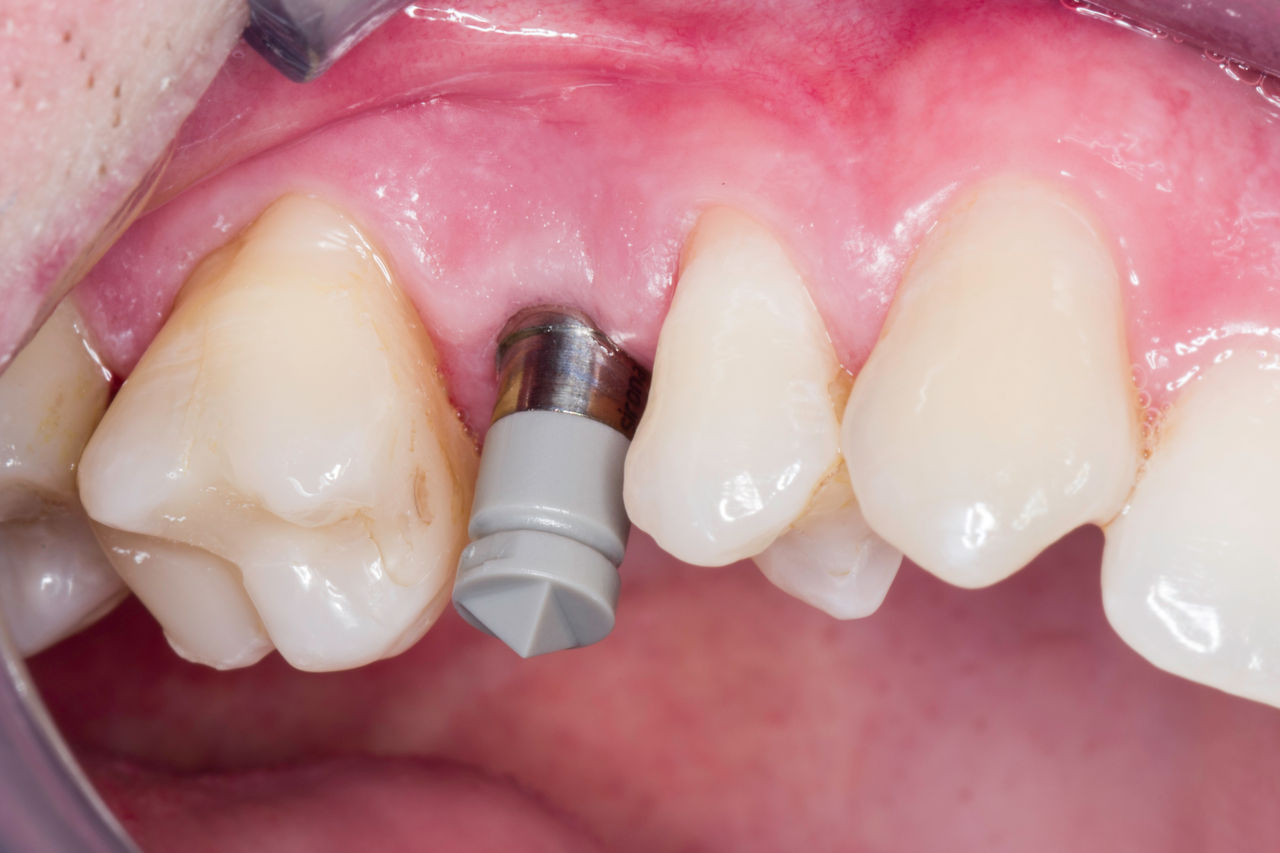

Before

Absence of tooth 15 due to a longitudinal fracture. Patient wanted to close the resulting tooth gap.

After

A high-quality glass-ceramic crown providing a highly esthetic and long-term stable restoration.